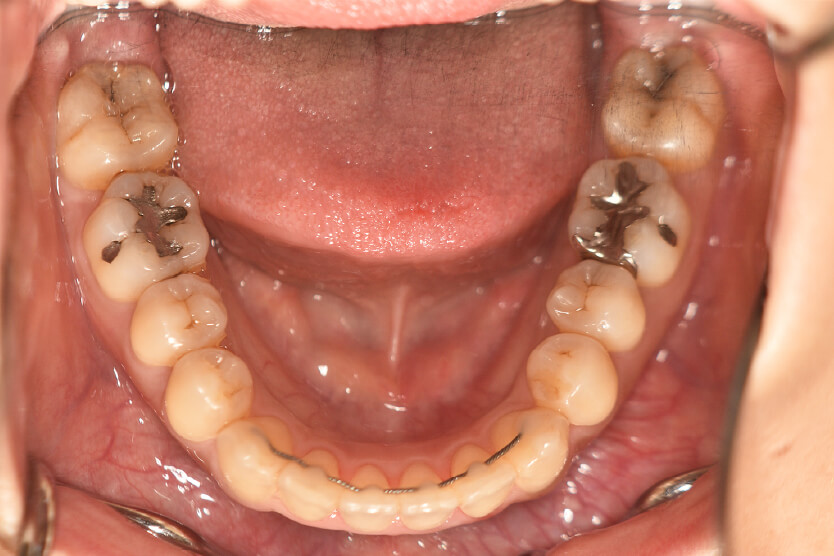

動的治療終了時

症例 症例 症例 症例

治療としては、上顎左右第一小臼歯の抜歯をし、セルフライゲーションブラケット装置(デーモンシステム)とマウスピース型矯正装置(インビザライン)で配列を行いました。

この際、上顎に歯科矯正用アンカースクリューを設置し上顎前歯部後退時の土台としました。

開咬については顎間ゴムの協力もあり改善され、口元も後退し、キレイな横顔になりました。

治療期間は2年4か月でした。